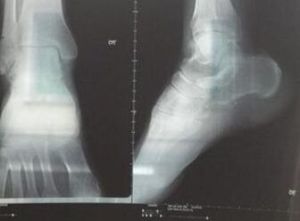

4.X射線檢查,可見關節間隙變窄軟骨下關節面硬化關節邊緣有程度不等骨刺形成。晚期可出現關節面不整,骨端變形,關節內有游離體。

本病是骨折或關節急性損傷過後,在較長時間內逐漸形成的。當受傷關節形成退行性變化時,將顯示關節間隙變窄骨端硬化,關節邊緣部骨贅形成關節內可能有游離體,還可因骨端生長發育障礙或骨關節損傷後而遺留肢體畸形,有時合併關節周圍軟組織內鈣化或骨化。該檢查方法簡便易行。CT